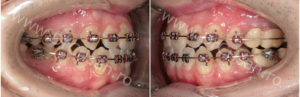

1) Aparat ortodontic inițial pentru aliniere și nivelare plan de ocluzie;

2) Intervenția chirurgicala cu fractura controlata a osului maxilar (osteotomie Le Fort I);

3) Continuare tratament cu aparat ortodontic restabilirea raporturilor ocluzale corecte.

Tratamentul ortodontic a continuat cu același aparat ortodontic cu care s-a început terapia. Raporturile ocluzale cadran stâng respectiv cadran drept.